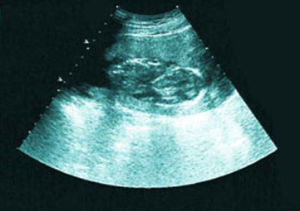

診斷鑑別

胎停育的B超檢查B超監測胚胎,胎兒發育,如≥6周無妊娠囊,或雖有妊娠囊但變形皺縮,當妊娠囊已≥4cm卻看不到胎芽,胎芽的頭臂長度≥1.5cm卻無胎心博動,即可判定胚胎或胎兒發育異常。後三種情況可以診斷為胎停育。

胎停育是指妊娠早期胚胎因某種原因所致發育停止。B超檢查表現為妊娠囊內胎芽或胎兒形態不整,無胎心搏動,或表現為妊娠囊枯萎。臨床屬於流產或死胎的範疇。造成胎停育的原因很多。

一般胚胎8周左右有胎心,胎停育現象在8~12周就有可能出現,所以建議孕婦8周左右最適宜去做B超,以便及早檢查胎兒和胎盤的發育情況。如果出現了胎心,大致可以放心。